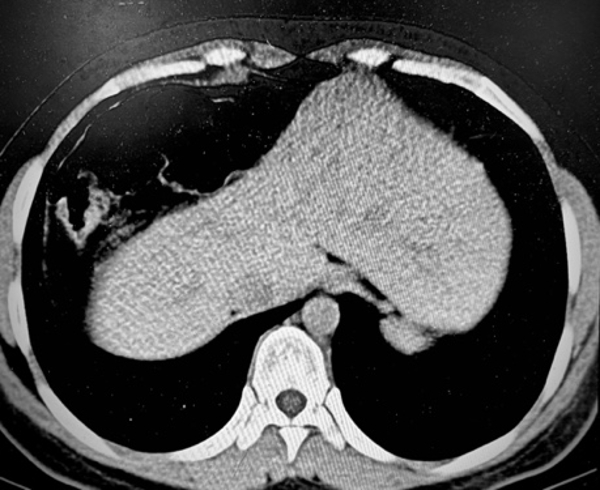

近日一位美丽的藏族姑娘因间断上腹及右上腹痛找到了援藏消化专家马师洋教授,患者在门诊已经先后化验了常规项目与超声、胃镜,但没有找到能够解释腹痛的病因。疼痛发作的时候非常明显,伴随腹胀、便秘。马师洋教授仔细询问了患者病情特点,建议患者完善腹部CT检查,在CT影像中可以看到充气的结肠影突入肝脏与横膈之间,这一表现支持间位结肠的诊断。

间位结肠系由希腊学者Demetrius Chilaiditi。于1910年首次报道,亦称Chilaiditi综合征,指结肠(多为肝曲)由肝前间隙或肝后间隙进入肝脏与横膈之间,其成因并不在结肠本身,肝脏下移和位置异常为其形成基础。常见肝脏韧带过长、薄弱、缺无等发育异常致肝脏下移,使肝膈间隙增大,以致结肠嵌入其间。间位结肠发病率为0.025%~0.28%,本病通常 无症状,部分患者表现为季肋部隐痛、厌食、腹胀、便秘,嵌入结肠发生梗阻或扭转时,可突发剧烈上腹痛、恶心呕吐、呼吸费力等症状,数小时 至数日后消失,多于活动后突然缓解,休息、通便、促进胃肠动力等内科保守治疗常可见效,内科保守治疗无效时,可考虑外科手术。